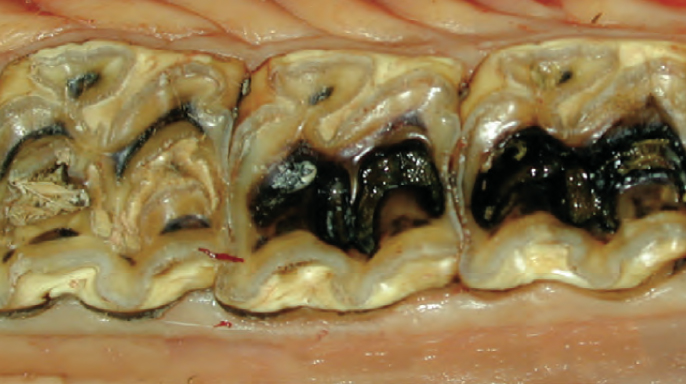

Autoři článku diskutují o významu remineralizace a demineralizace v procesu vzniku zubního kazu.

Zubní kaz je celosvětově nejrozšířenějším neinfekčním onemocněním. Jedním z důvodů je skutečnost, že jeho počáteční stadia, která lze považovat za subklinické projevy kariézního procesu, jsou často řešena přístupem „sledovat a čekat“. Tento přístup však nese riziko progrese kazu³ a v závažných případech může vést i k vážným zdravotním komplikacím.

Výplně, respektive kompozity využívám v případech rozsáhlých či klinicky významných infundibulárních kazů, které se vyskytují na trvalých maxilárních premolárech a molárech tvořících dentici koní.